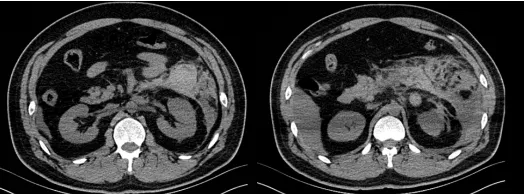

近日,我院肝胆外科手术团队在副院长卜献民教授的带领下,成功开展了两例达芬奇机器…